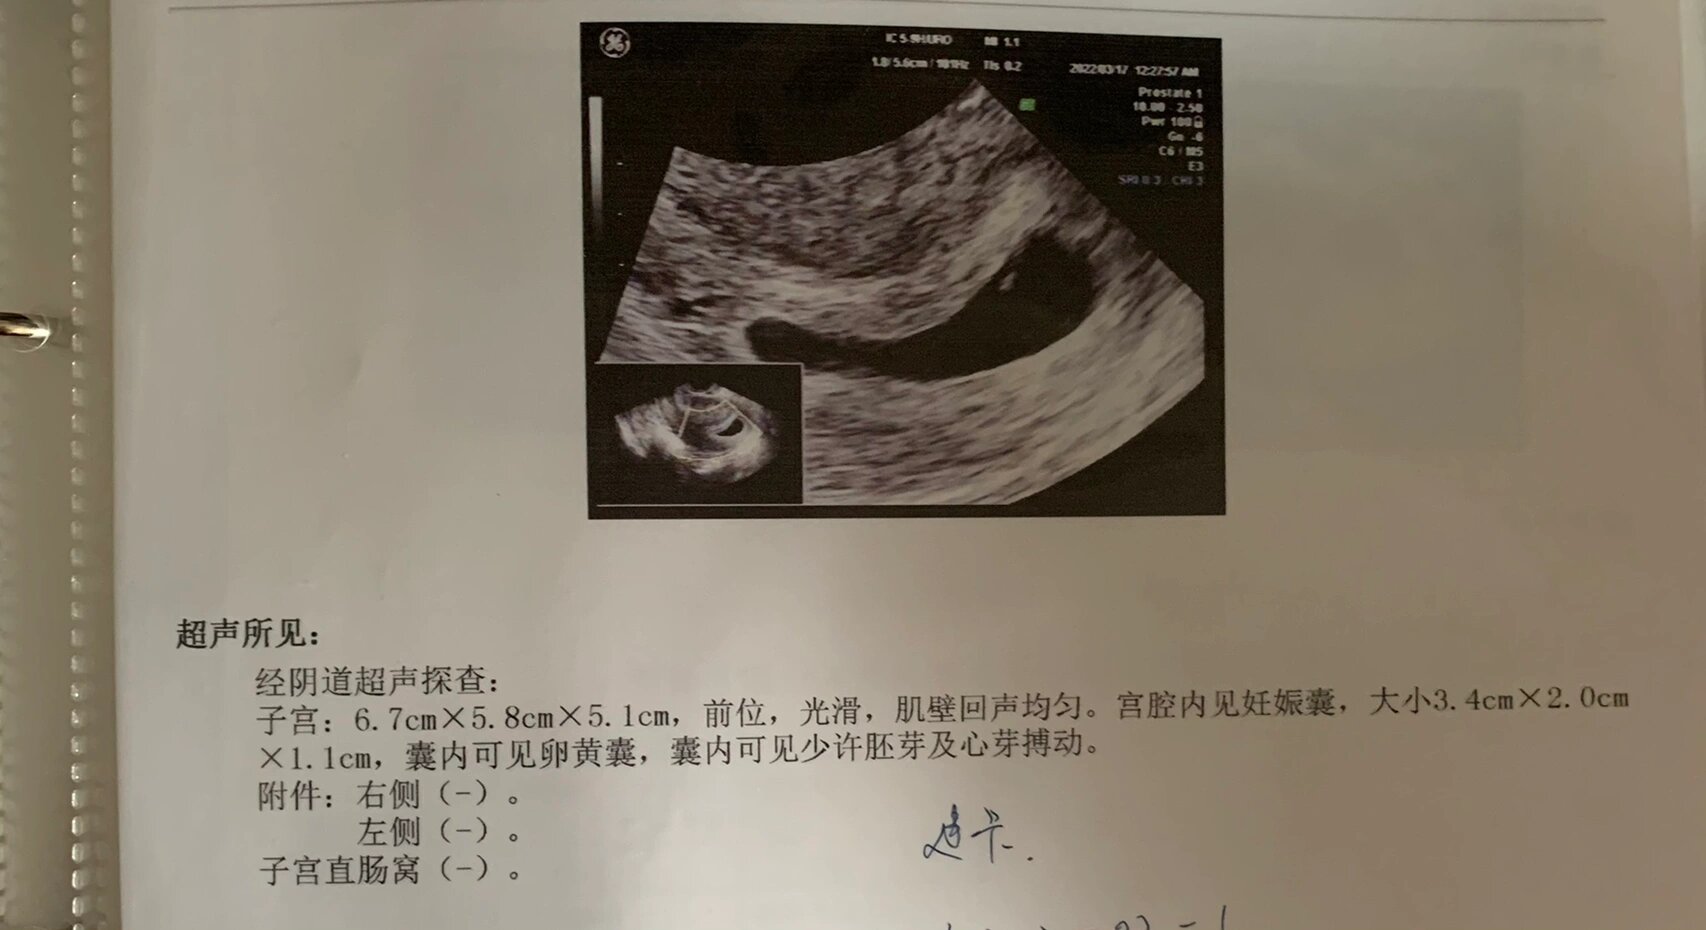

27那天,我怀着忐忑的心情去复查,b超显示孕囊长大了,还有卵黄囊,我